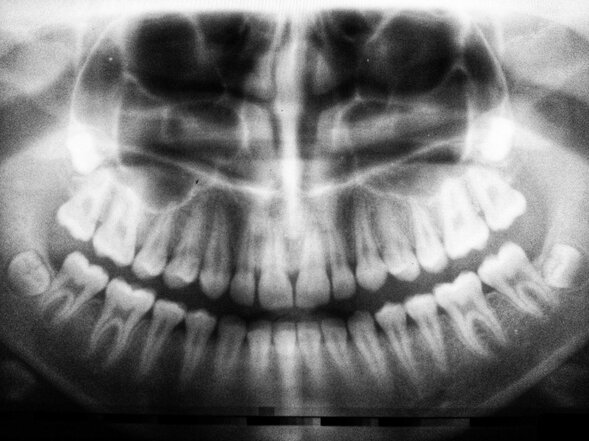

Pigskin Pick 'Em. FREE to play. Create up to 5 entries and compete for 57 prizes worth $100K. Make Your Picks. Bold prediction ... Back Molar Filling Dental Fillings Procedure

Step By Step Dental Filling Cavity Filling Tooth Filling Cusp

Tooth Cavity Filling